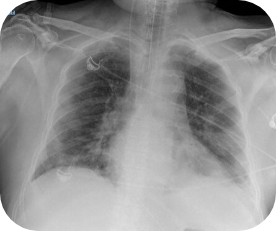

Chest X-ray:

Patchy areas of consolidation